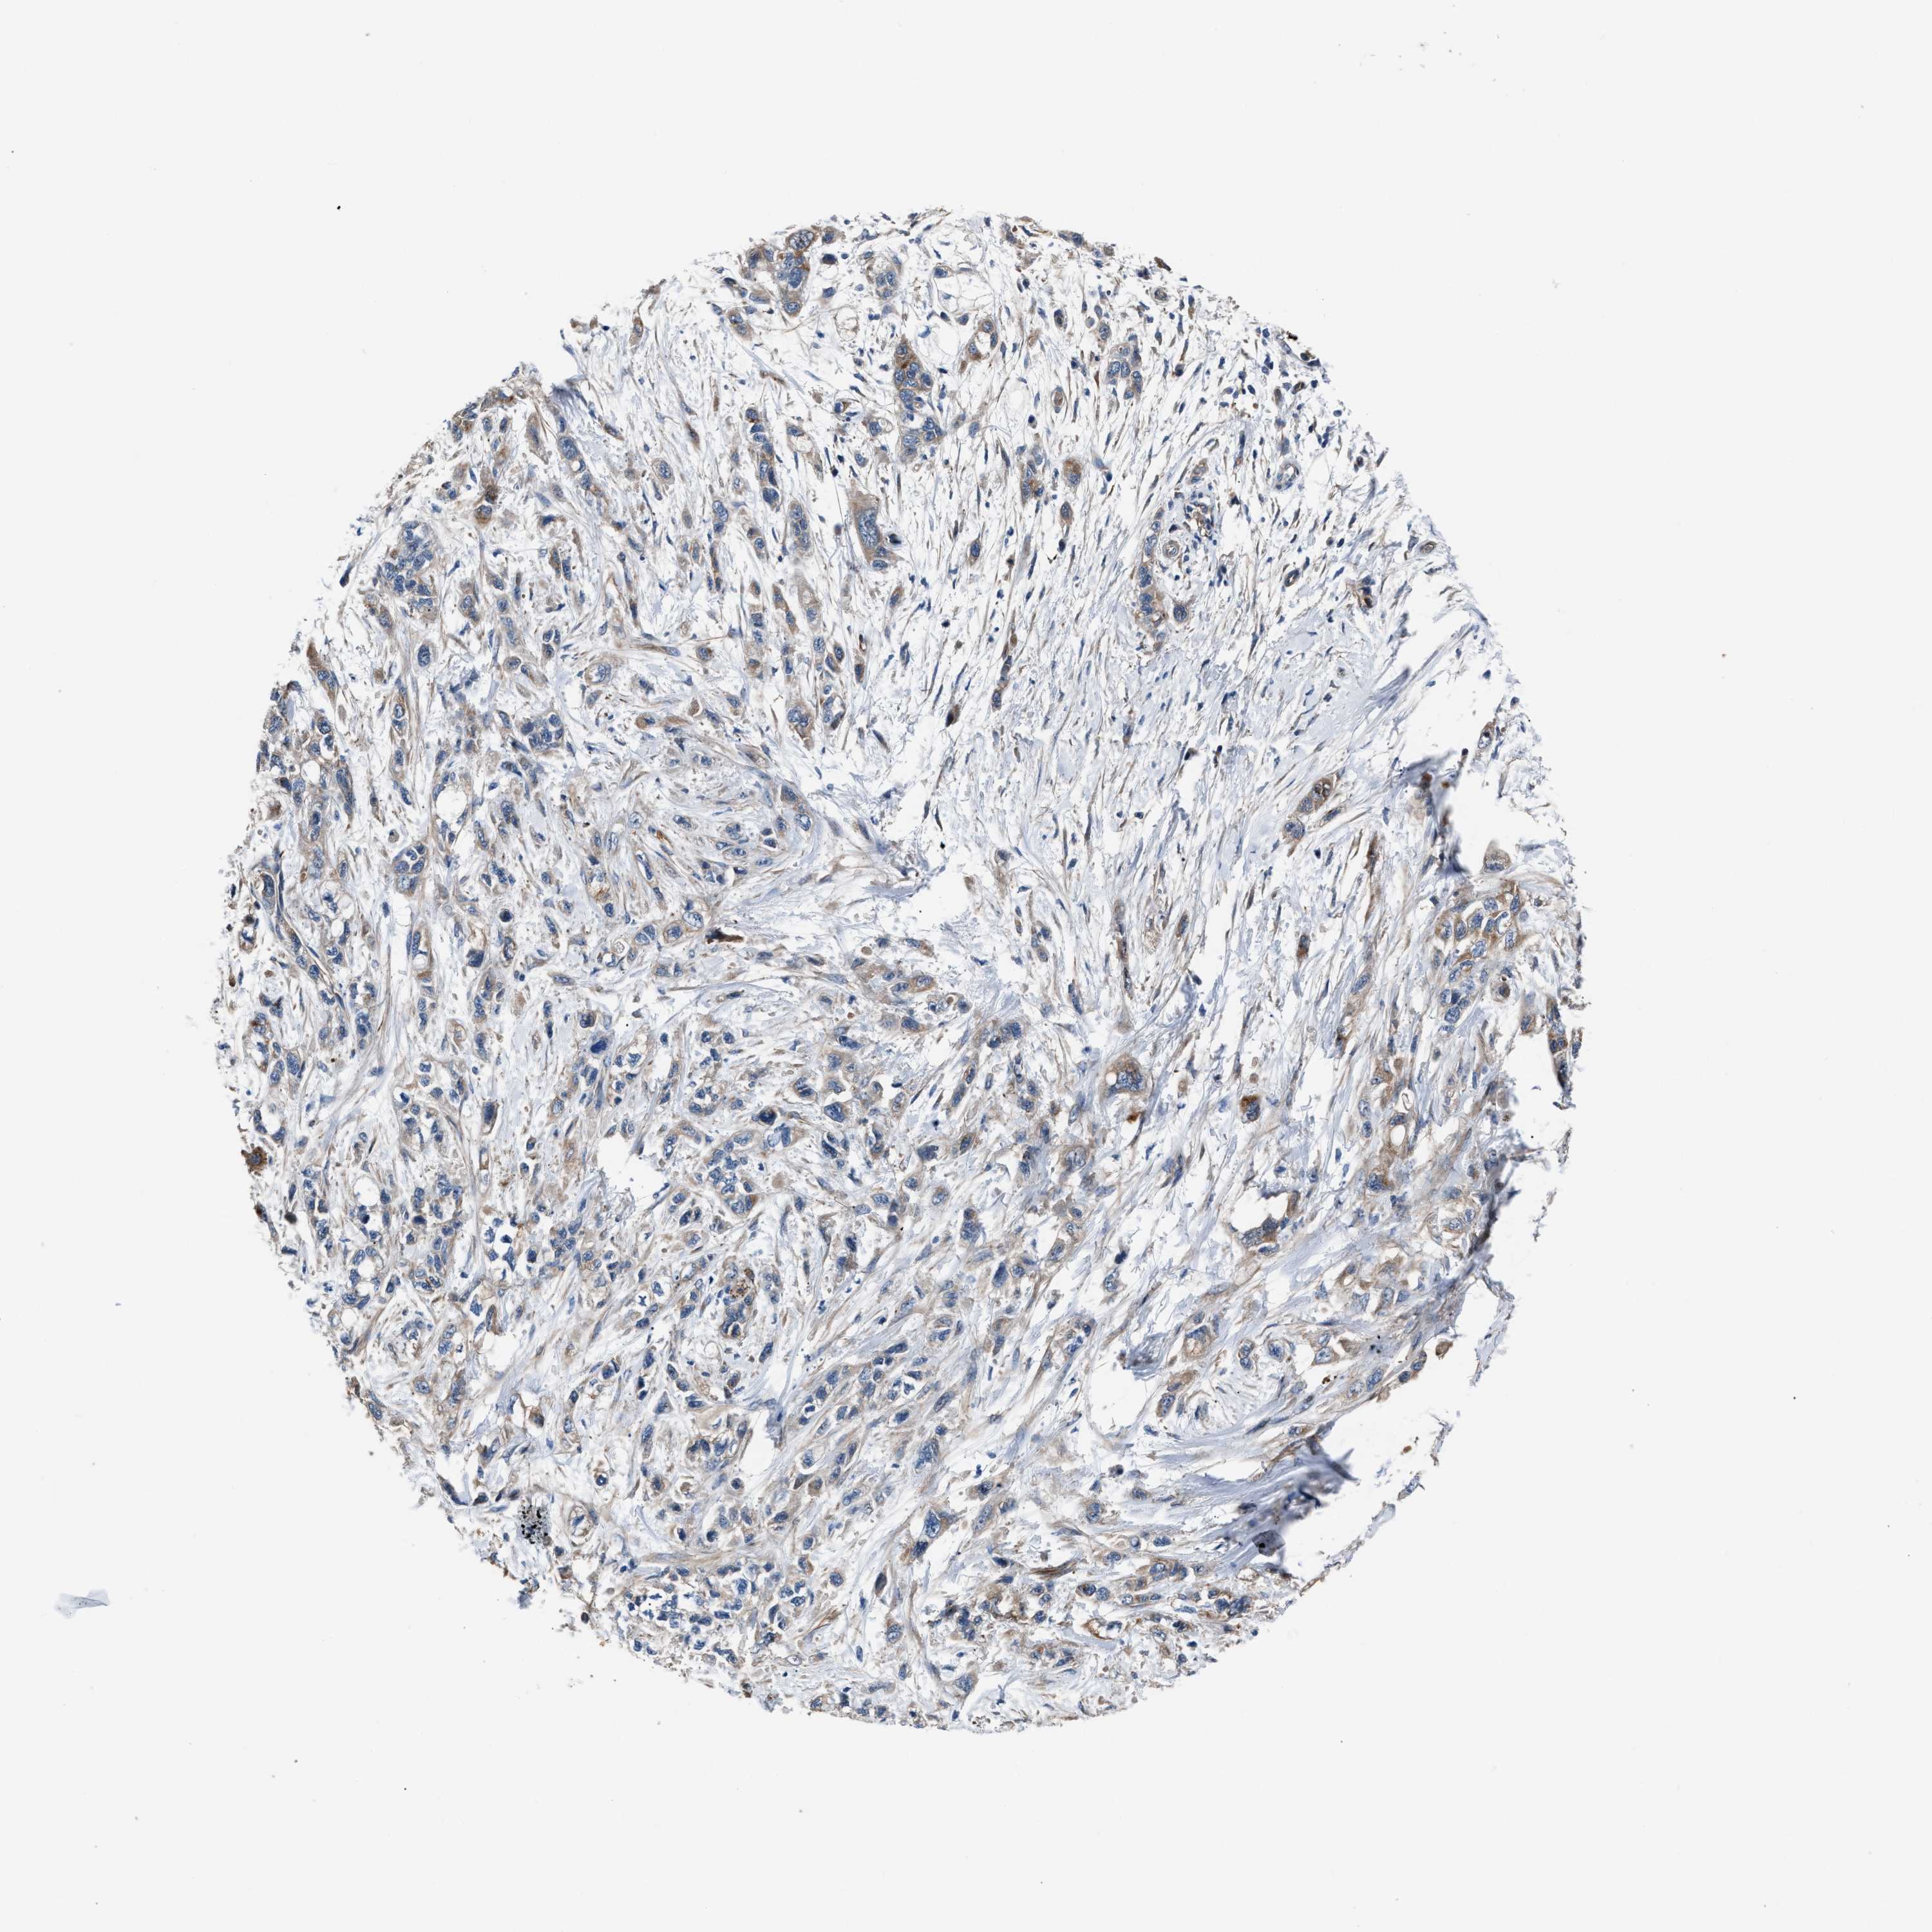

PANCREATIC CANCER - Protein expressioni

A mouse-over function shows sample information and annotation data. Click on an image to view it in a full screen mode. Samples can be filtered based on level of antibody staining by selecting one or several of the following categories: high, medium, low and not detected. The assay and annotation is described here.

Note that samples used for immunohistochemistry by the Human Protein Atlas do not correspond to samples in the TCGA dataset.

Antibody stainingi

Antibody staining in the annotated cell types in the current human tissue is reported as not detected, low, medium, or high, based on conventional immunohistochemistry profiling in selected tissues. This score is based on the combination of the staining intensity and fraction of stained cells.

Each image is clickable and will lead to virtual microscopy that enables deeper exploration of all samples and also displays staining intensity scores, fraction scores and subcellular localization as well as patient and tissue information for each sample.

Antibody HPA020255

Antibody HPA026686

Antibody CAB013512

Staining

High

Medium

Low

Not detected

Intensity

Strong

Moderate

Weak

Negative

Quantity

>75%

75%-25%

<25%

None

Location

Nuclear

Cytoplasmic/membranous

Cytoplasmic/membranous,nuclear

Adenocarcinoma, NOS

Adenocarcinoma, metastatic, NOS